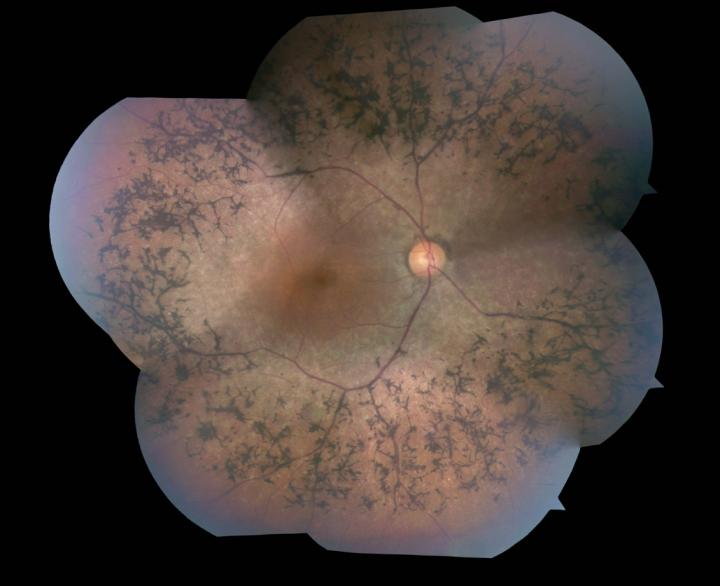

image: Image of retina from right eye of a patient with retinitis pigmentosa due to phosphodiesterase deficiency. Intraretinal pigments (pink) are seen in areas of photoreceptor loss. view more

Credit: The Jonas Children's Vision Care, Columbia University Medical Center